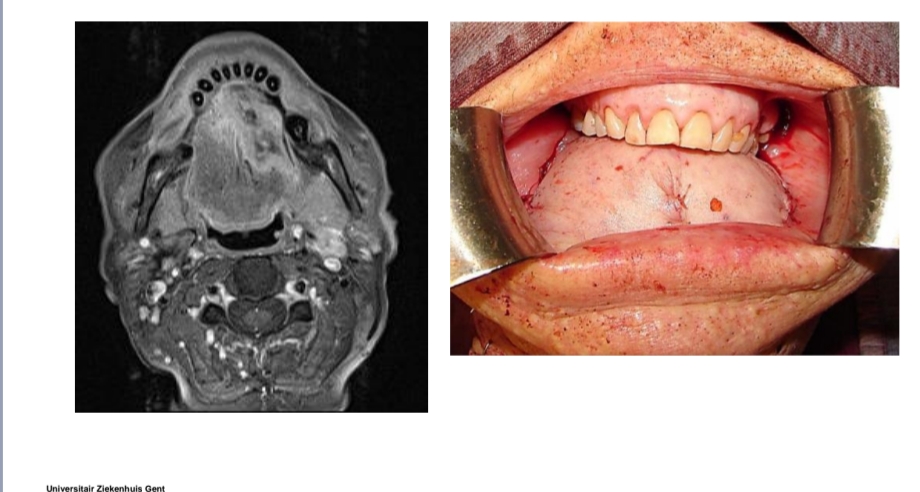

Mondbodem- en grotere tongtumoren

Primair sluiten zorgt voor mobiliteitsbeperking

(oppervlakteverkleining)

Reconstructie van mucosaal oppervlak (niet spier) is nodig voor

herstel tongmobiliteit

Meestal vrije voorarmflap (radialisflap)

Beenderige resectie: partiële mandibulectomie

Mondbodem, trigonum retromolare, gingiva onderkaak (T4)-

→ reconstructie vr functie te verkrijgen

Beenderige reconstructie